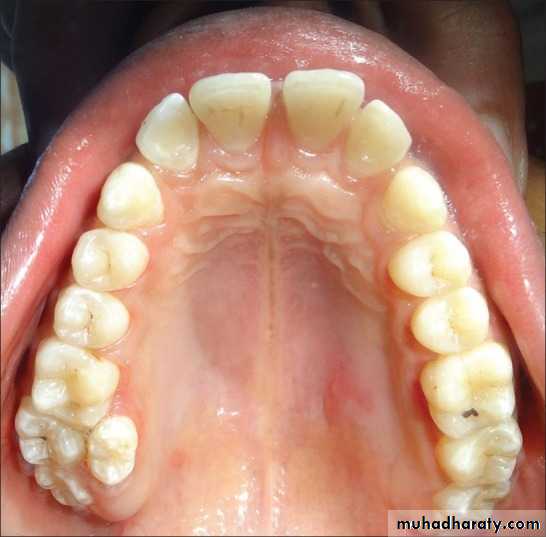

4- Premature loss of deciduous teeth

The early loss of primary teeth should be considered as a “Malocclusion Maker”Deciduous teeth not only serve as organs of mastication, but as spacesavers for permanent teeth. Loss of a deciduous 2nd molar will lead to mesial driftof the 1st permanent molar and blocking of

erupting 2nd premolars.In this cases appropriate

space maintainers should be given.